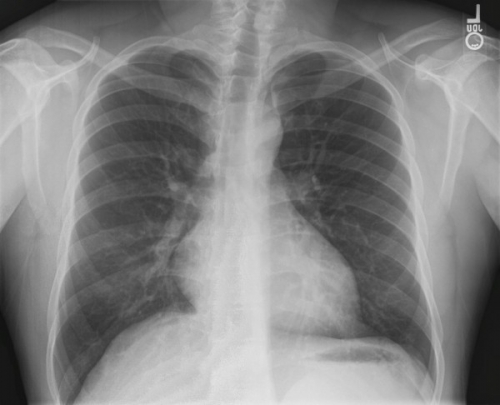

Tool to train medical student's eyes as to what a normal chest x-ray looks like, with over 500 consecutive normal images.